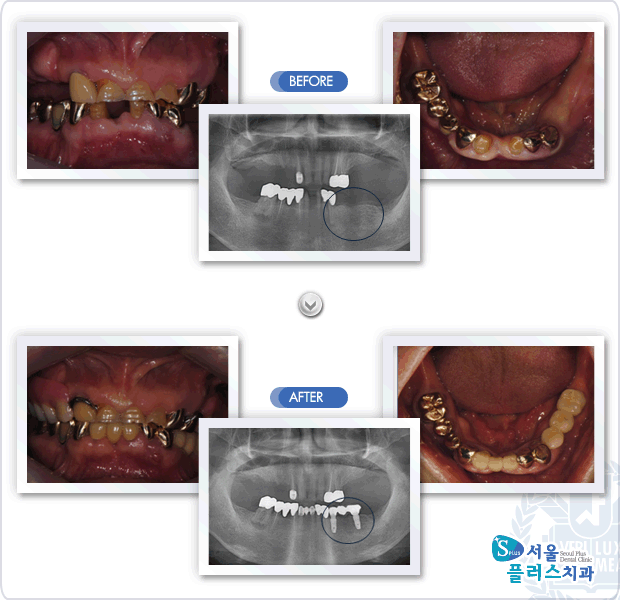

[임플란트] 하악 전치부와 하악 좌측 구치부의 상실로 내원